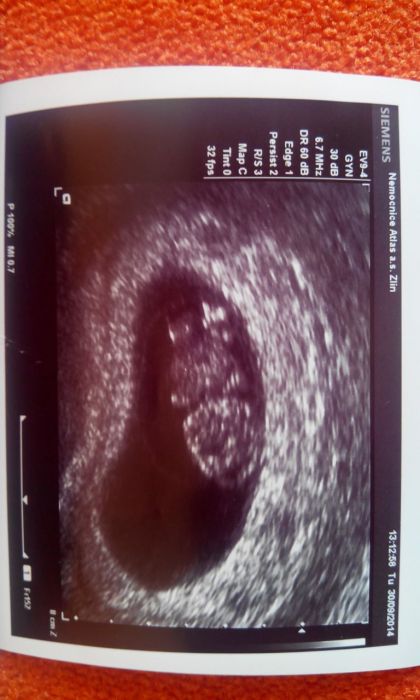

Ahoj holky, můžu se k vám přidat? Termín porodu podle menstruace mám 3.5. Dnes bych měla být 10+4 a na screening jdu 20.10. Strašně se těším, ale zároveň i bojím. Snad bude miminko v pořádku. Od začátku bojuji s krvácením, ale už pár dní to přešlo, tak snad to bude dobré. Na krev jsem byla v pondělí, ale na screeningu mi asi budou brát taky, jdu totiž jinam. Jsem ze Zlína. Držím všem pěsti. :) Fotka je z 9+1.Takový gumový medvídek. :)